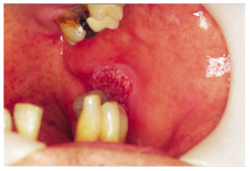

What Some Oral (Mouth) May Cancers Look Like

A shallow

ulcer on the lower lip

A speckled ulcer

Tongue cancer

A red

patch under the tongue

These photographs are not meant to scare you. Just to remind you about what some oral cancers may look like. Get a doc-check if anything at all doesn’t seem right to you.